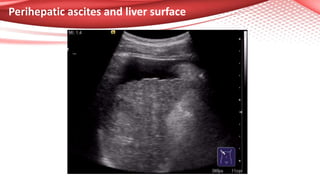

Perihepatic ascites and liver surface